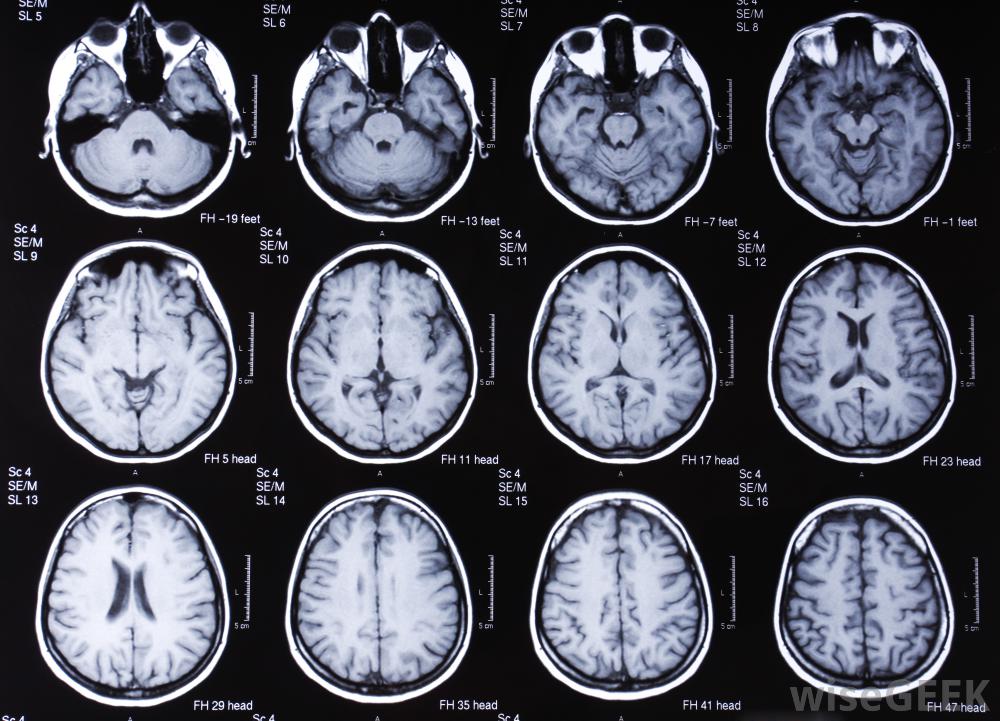

什么是開放式核磁共振成像(Open MRI)?

開放式核磁共振成像(MRI)是原始磁共振成像(MRI)設備的一種高級形式。自20世紀80年代開始使用,MRI掃描通過人體發送的電磁波和無線電波的強度高達地球磁場的3萬倍。常規MRI是一種大的封閉式磁鐵,患者在進行MRI掃描時躺在里面...